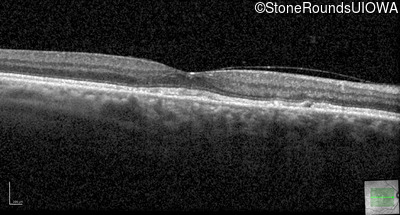

Optical Coherence Tomography - Right - 20/20

Exemplar / OCT Stack

OCT Stack